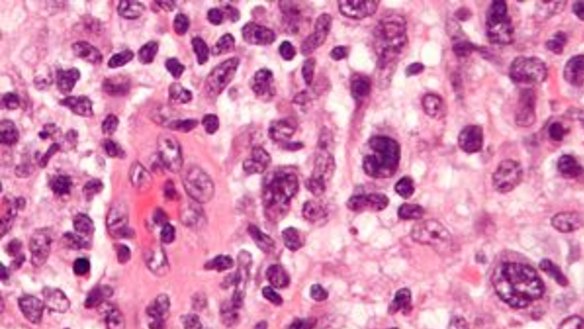

Microgram of anaplastic large cell lymphoma.Wikipedia

All cases have involved textured implants, and the greater the texture the higher the risk, data suggests.